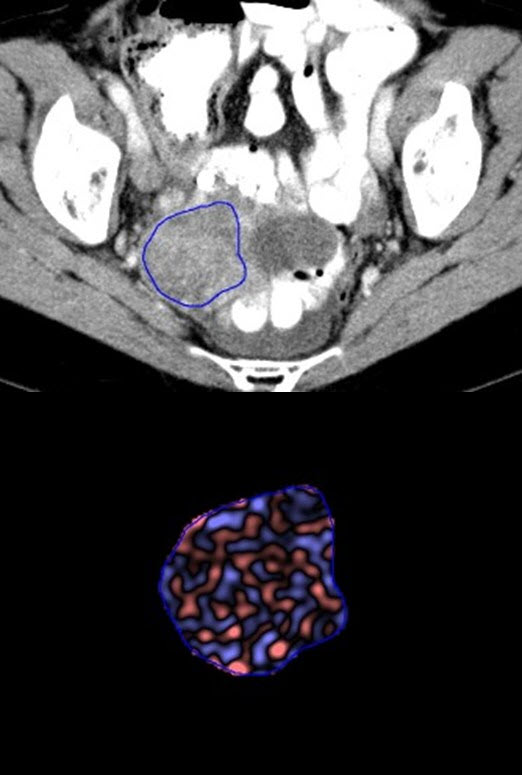

Incidental adnexal lesions are common, reported in up to 18% of postmenopausal women. While majority of incidental adnexal lesions are benign cysts, correct follow-up is important because some can be ovarian cancer. Ovarian cancer is the leading cause of death among gynecological cancers and majority of them are diagnosed at an advanced stage, resulting in a poor prognosis. This makes accurate characterization and management of incidental adnexal masses vital. At present, the management of incidental adnexal lesions is based on low-level evidence and depends on patient’s age, size of the lesion and imaging features. However, these lesions commonly remain indeterminate as difficult to characterize when they are first detected. Correct diagnosis either requires additional imaging follow-up with ultrasound or MRI, serial imaging follow-up or invasive procedures for pathologic correlation. Imaging has assumed a central role in clinical management of various neoplastic and non-neoplastic conditions. Every pixel in a medical image has data that is not evaluable by simple visual inspection, such as subtle variations in attenuation indicative of tumor heterogeneity. However, this information can be extracted by processing the images with specialized algorithms and softwares. The concept of texture analysis has been studied in tumors like lung, renal, colorectal, ovarian, esophageal and head and neck cancers with encouraging results regarding characterization and prognostication of cancers; however, the literature available is scant and heterogeneous. Texture analysis can potentially be used to characterize the incidental adnexal lesions and predict their outcome. This would help in optimal management of these lesions. The purpose of this study is to use CT texture analysis for characterization and prognostication of incidental adnexal lesions.